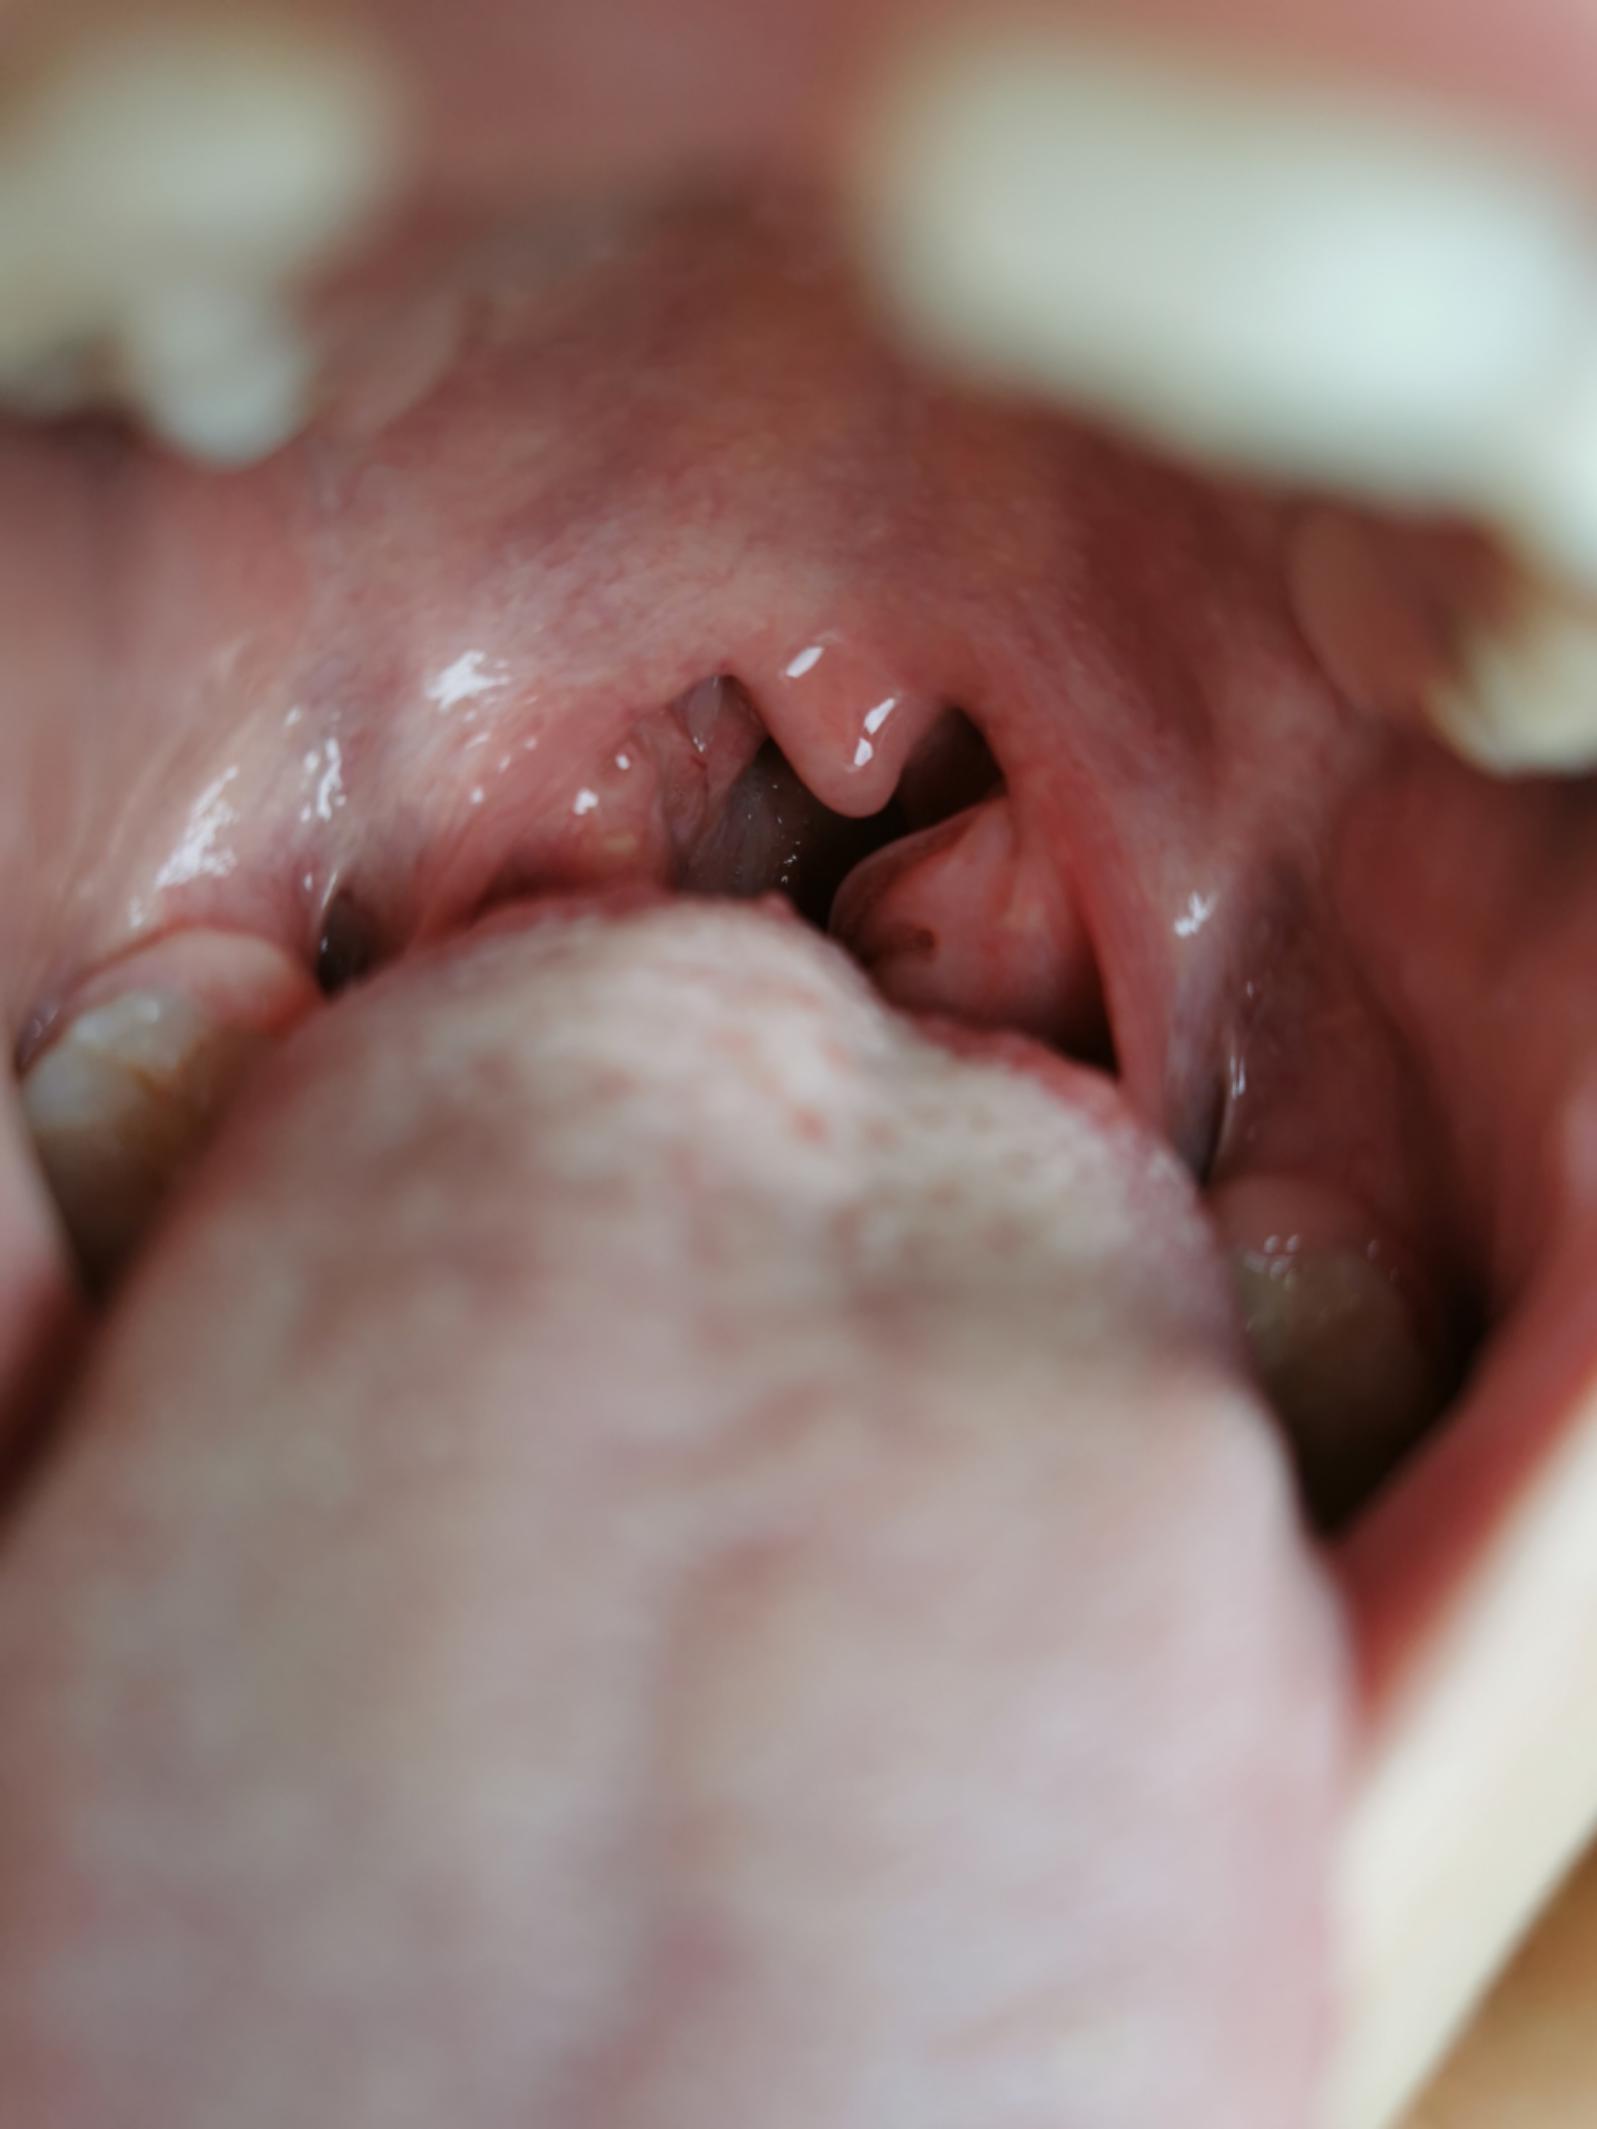

上学日 ,孩子晚饭后呕吐咳嗽发烧38.7℃,没有以往喘了,呼吸平息了许多,挂了急诊,医生检查出来扁桃体肿大快接近三度,“医生说这个情况过度肿大,反复发炎的话要手术割除的,我被吓到了,孩子吊完针后晚上11点了,我拿了西药就回家了。”